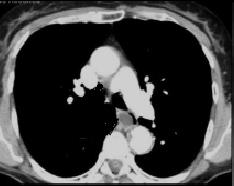

Images

radiologiques de la sclerodermie de oesophage en TDM

coupe axiale et coronal fenetre parenchymateus .Oesophage

en amont

et en aval de la region slerosante sont dilate